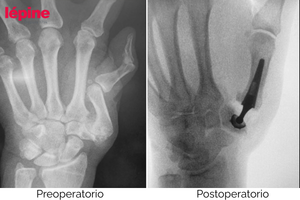

Casos clínicos: antes y después del tratamiento

Las siguientes imágenes muestran casos clínicos reales que ilustran la evolución del paciente antes y después del tratamiento con implantes ortopédicos de mano.

Estos resultados reflejan el objetivo principal de nuestras soluciones: restaurar la función, reducir el dolor y mejorar la calidad de vida, siempre mediante evaluación y seguimiento médico especializado.